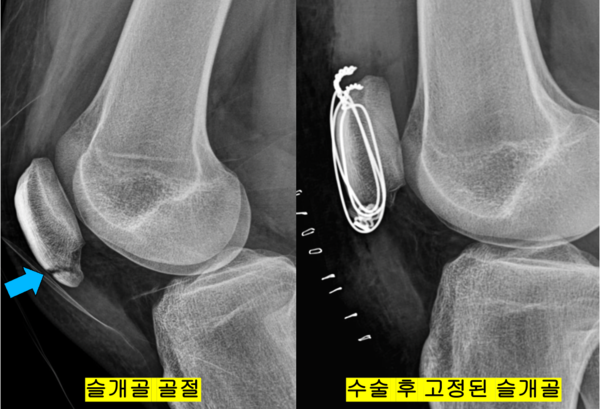

Q. 카이리 어빙은 2015년 파이널 경기 도중 슬개골이 골절되는 부상을 입었던 바 있습니다. 슬개골 골절과 슬개건 부상은 정확하게 구분돼야 할 것 같은데요. 슬개골 골절은 어떤 부상일까요?

A. 슬개골 골절 부상은 슬개건의 파열이 아니라 슬개골이 파열되는 부상입니다. 넘어질 때 슬개골에 직접적인 충격이 실려 골절이 발생하는 경우가 가장 흔하지만, 운동선수들의 경우 순간적으로 대퇴대퇴사두근이 수축할 때, 큰 부하가 건에 전해지지 않고 슬개골에 전해질 경우 발생할 수 있습니다. 이때는 뼈가 부셔지는 골절이 발생할 수 있습니다. 그러나 슬개골 부상의 경우에는 건부상에 비해 조금 더 좋은 결과를 기대할 수 있습니다. 골절의 경우에는 수술로 뼈의 완전한 유합을 얻게 되면 재발없이 “완치"가 가능할 수 있기 때문입니다.